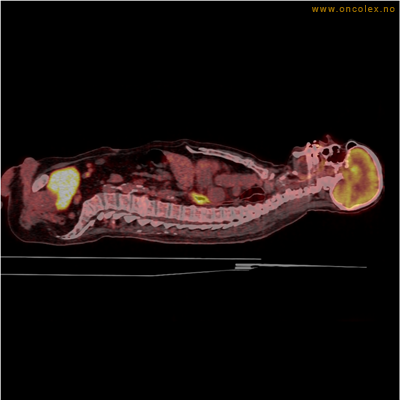

Eksempler på funn

Vev som tar opp mer radioaktivt stoff, synes som hvite områder som lyser opp mer i forhold til annet vev som tar opp mindre sukker.

Moderat opptak i bløtvevssarkom venstre halvdel av brystkassen. Områder med lavere opptak antas å skyldes dels betennelse som skyldes svulsten, dels svulstnekrose.

Moderat opptak av FDG i bløtvevssarkom venstre halvdel av brystkassen. Områder med lavere opptak antas å skyldes dels betennelse som skyldes svulst, dels svulstnekrose.